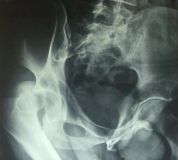

4. Posterior dislocation of the right hip with posterior acetabulum fracture in a 40-year-old male.

Treatment: 1st stage; closed reduction of the dislocation 2nd stage; open reduction of the acetabulum fracture with internal fixation

Ι. Obturator view of the right acetabulum shows the dislocation of the right hip II. Obturator x-ray right acetabulum shows the reduction of the hip, the red arrow shows the fracture III. Iliac x-ray acetabulum after the procedure shows the implant work (the patient referred to Mr. Antonios Papasotiriou who fixed the acetabulum)